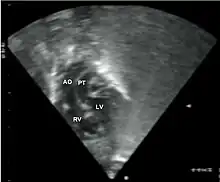

Echocardiogram: An echocardiogram is an ultrasound of the heart which accurately assesses the heart’s structure and function, and can show the specific features of TGA, if present. This imaging modality allows for the definitive diagnosis of TGA to be made. [8]

- Echocardiography of a complex transposition with a ventricular septal defect and pulmonary stenosis.

Abbreviations: LV and RV=left and right ventricle, PT=pulmonary trunk, VSD=ventricular septal defect, PS=pulmonary stenosis. - Echocardiogram in transposition of the great arteries. This subcostal view shows the left ventricle giving rise to a vessel that bifurcates, which is thus identified as the pulmonary artery.